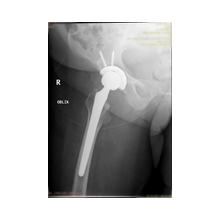

Peki kalça protezi ameliyatın da neler yapıyoruz? Diz protezi ameliyatındaki benzer aşamaları uyguluyoruz. Kalça eklemi dize göre yapısal olarak ve çalışma sistemi olarak farklıdır. Kalça eklemi bir yuva ve onun içinde hareket eden femur başı dediğimiz bir toptan oluşur. Kalça eklemi kireçlenmesinde bu baş ve yuva yüzeyindeki kıkırdakların aşınması sonucu başın yuvarlaklığı kaybolur, sonuçta ağrı ve hareket kısıtlılığı ortaya çıkar. Bu yüzeyleri değiştirirken öncelikle bu başı kesip atıyoruz. Daha sonra yuvayı yine kılavuzlarla oyup uygun büyüklükteki protezi sıkıştırdıktan sonra en az 2 vida ile kemiğe adapte ediyoruz. Daha sonra alt uyluk kemiğini yine kılavuzlar yardımı ile oyduktan sonra kemiğe adapte ediyoruz ve sistemi birleştiriyoruz.

Görüntüleri büyütmek için üzerine tıklayınız.